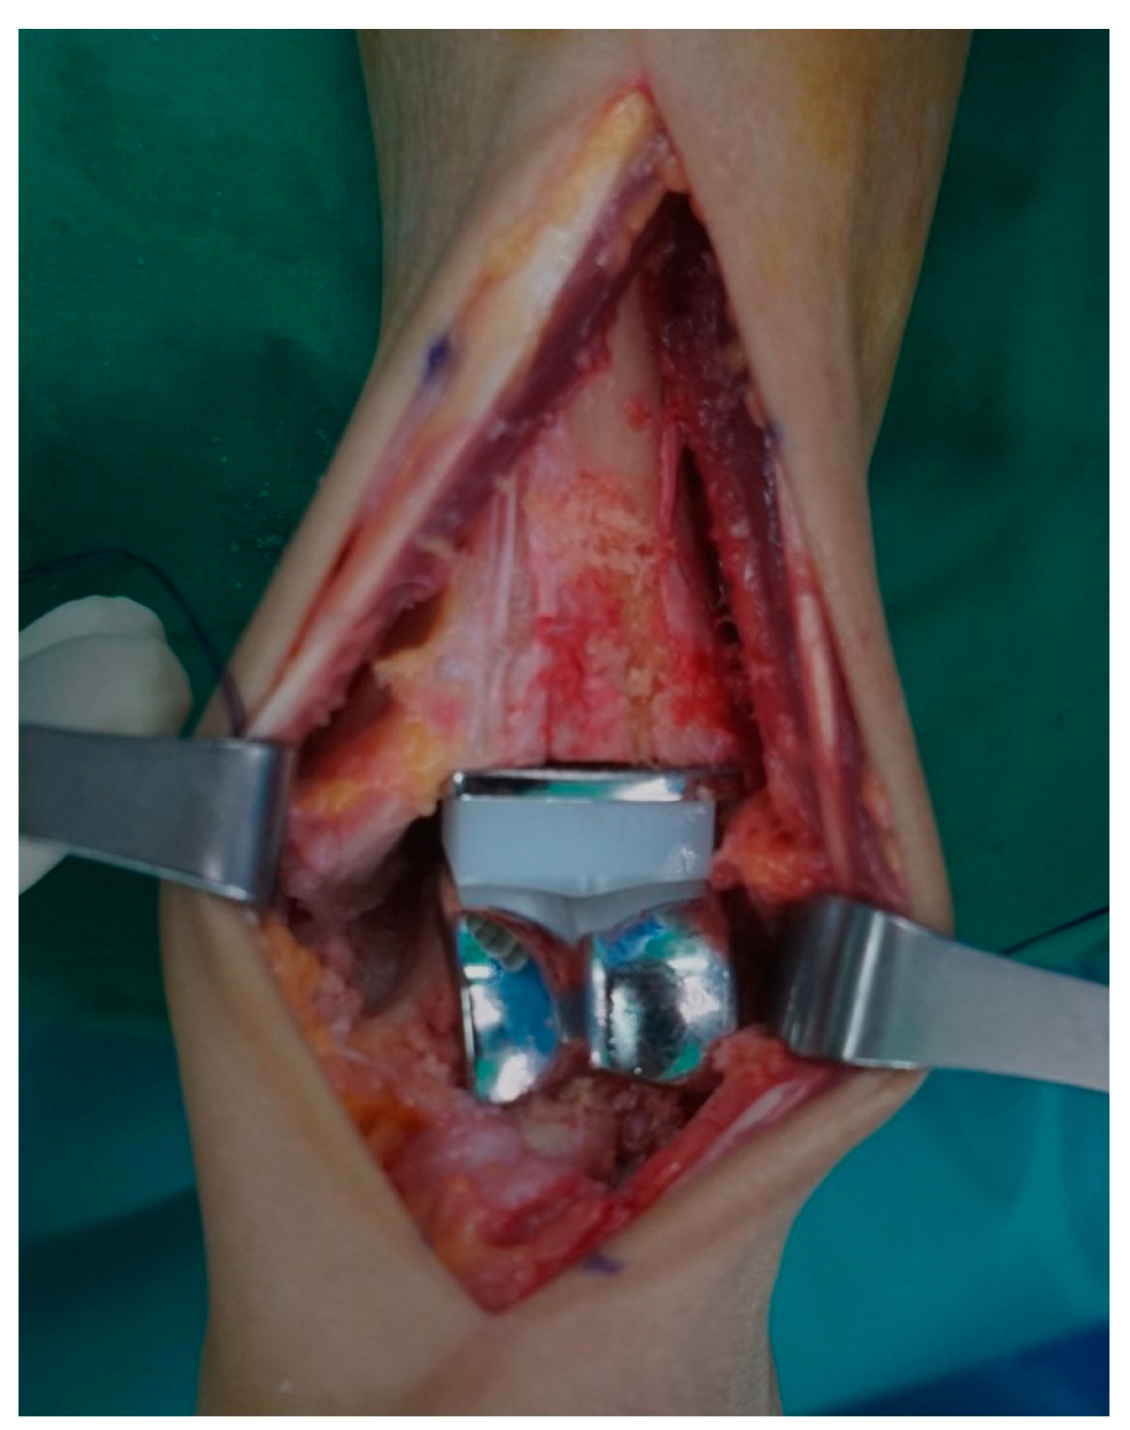

From January 2017 to June 2023, a total of 34 patients diagnosed with end-stage ankle RA who underwent TAA and were followed for 2 years were included in this study. A total of 16 patients without the modification of perioperative anti-rheumatic medications from January 2017 to April 2020 were classified into the uncontrolled group. Consecutively, 18 patients with the modification of perioperative anti-rheumatic medications from May 2020 to June 2023 were classified into the controlled group. All surgeries were performed by a single surgeon using a third-generation three-component mobile-bearing implant system (Zenith™; Corin, Cirencester, UK) (Figure 1 and Figure 2). The modification of perioperative anti-rheumatic medications was performed according to an established guideline [17] used in total hip and knee arthroplasty.

Figure 1. (A,B) Preoperative and (C,D) postoperative radiographs in a 68-year-old female with total ankle arthroplasty for end-stage rheumatoid arthritis.